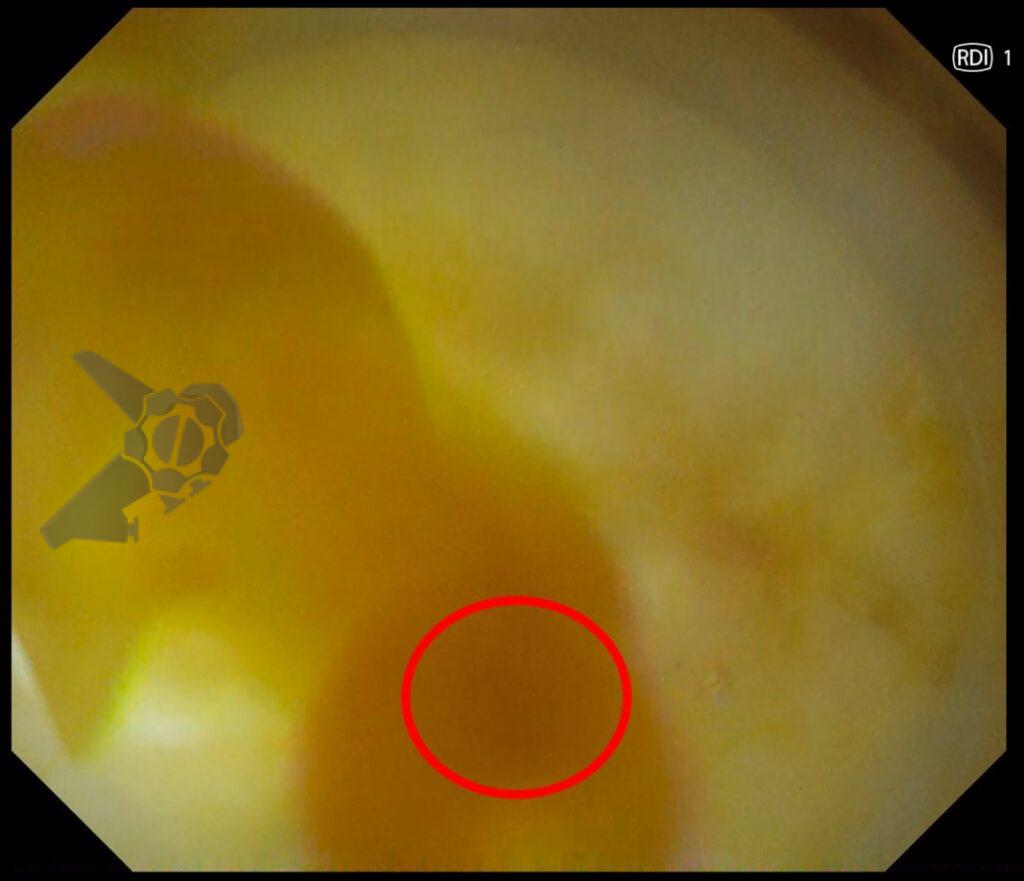

2. RDI (Red Dichromatic Imaging)

Essa tecnologia aplica os mesmos princípios do NBI, ou seja, são colocados filtros de luz. A diferença é que o RDI usa filtros de comprimentos de onda mais longos objetivando melhorar a visualização dos vasos mais profundos. As áreas com maior concentração de hemácias ficam com a cor laranja ou amarelo escuro, enquanto as áreas com menor densidade, ficam amarelas claras. Isso ajuda na hora de identificar o foco de sangramento ativo durante as ressecções endoscópicas (ESD ou mucosectomia), diminuindo o tempo para atingir uma coagulação adequada.

Fonte: Osaka International Cancer Institute.